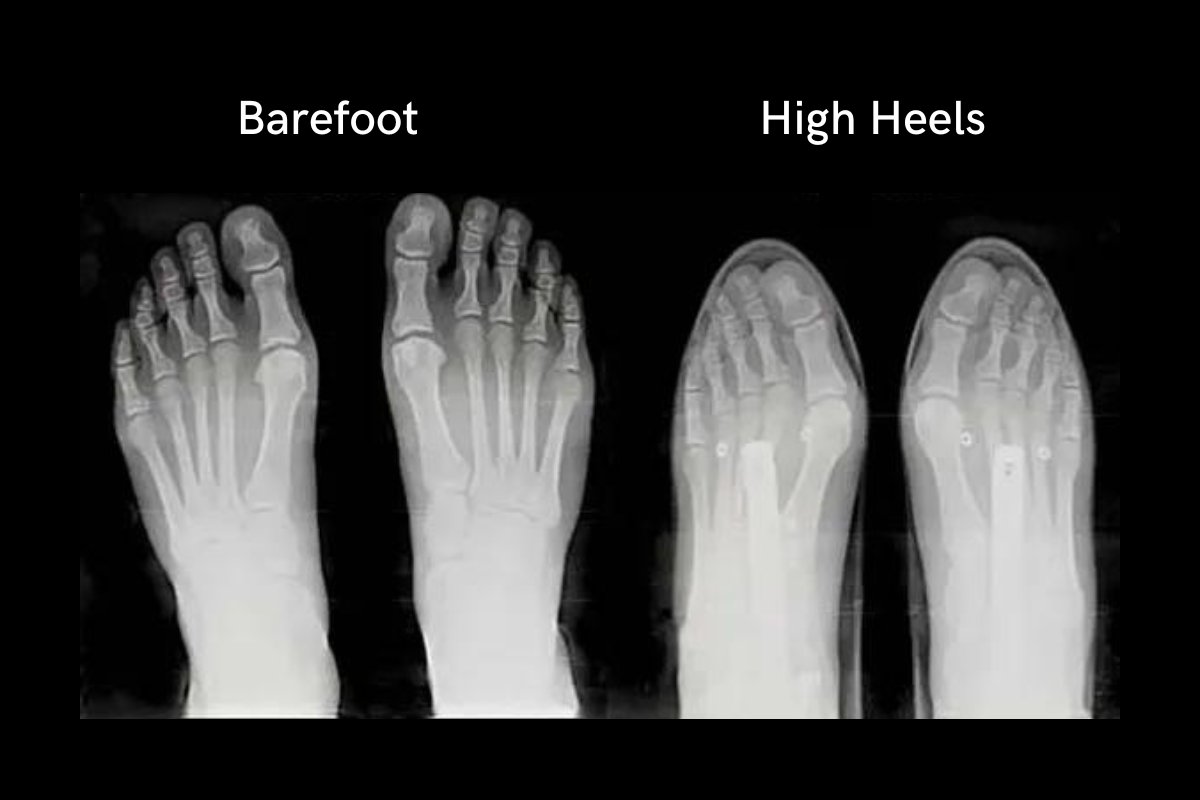

- Risks of sh*t shoes

- A WIDE toe box